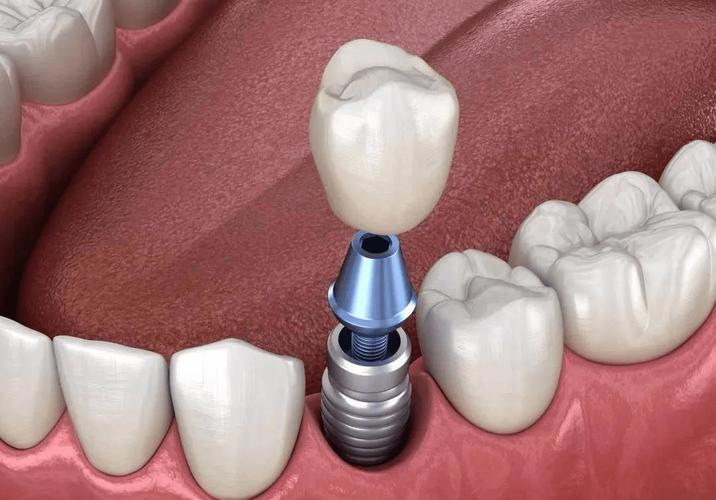

什么是种植牙?

- 将钛合金种植体植入牙槽骨,模拟牙根,再安装牙冠,恢复咀嚼功能。

种植牙流程(传统 vs 即刻):

| 植入种植体 | 骨愈合后手术植入 | 拔牙同期植入 |